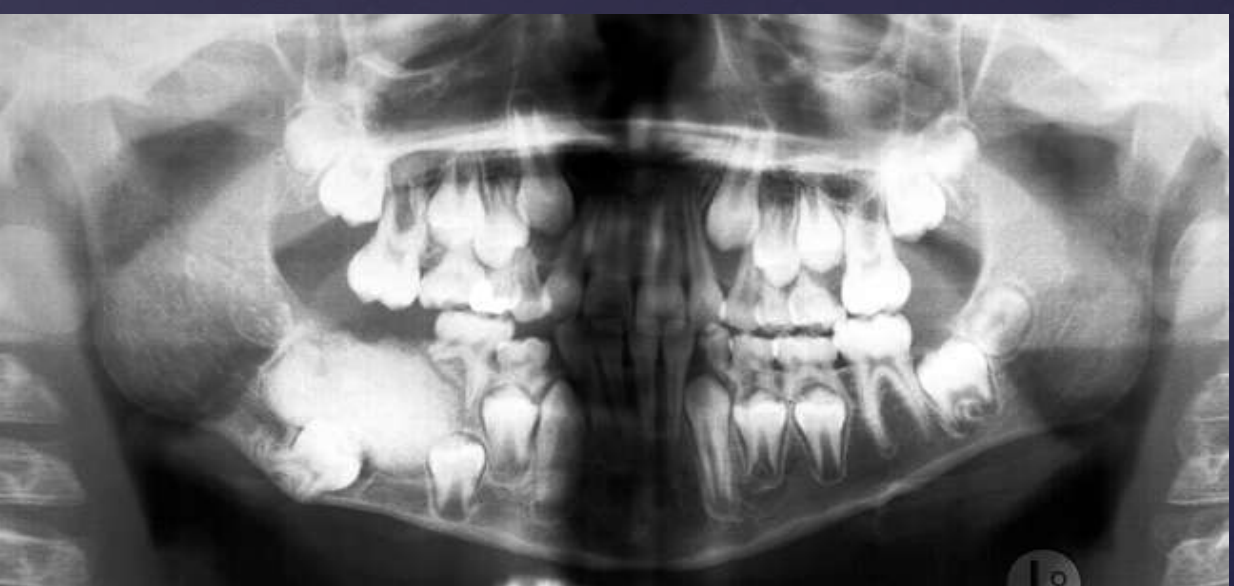

how do ameloblastomas radiographically present?

well circumscribed, corticated

radiolucent

unilocular/multilocular (coarse/curved septae)

expansile

Tooth displacement/root resorption

ameloblastomas

ameloblastoma

Pericoronal/mural; impacted tooth

Displacement of #32

Osseous expansion

Thinning of cortices

Displacement of inferior alveolar nerve canal

Multilocular

Root resorption

Thinning of inferior mandibular border

Septae appear coarse

Displacement of teeth